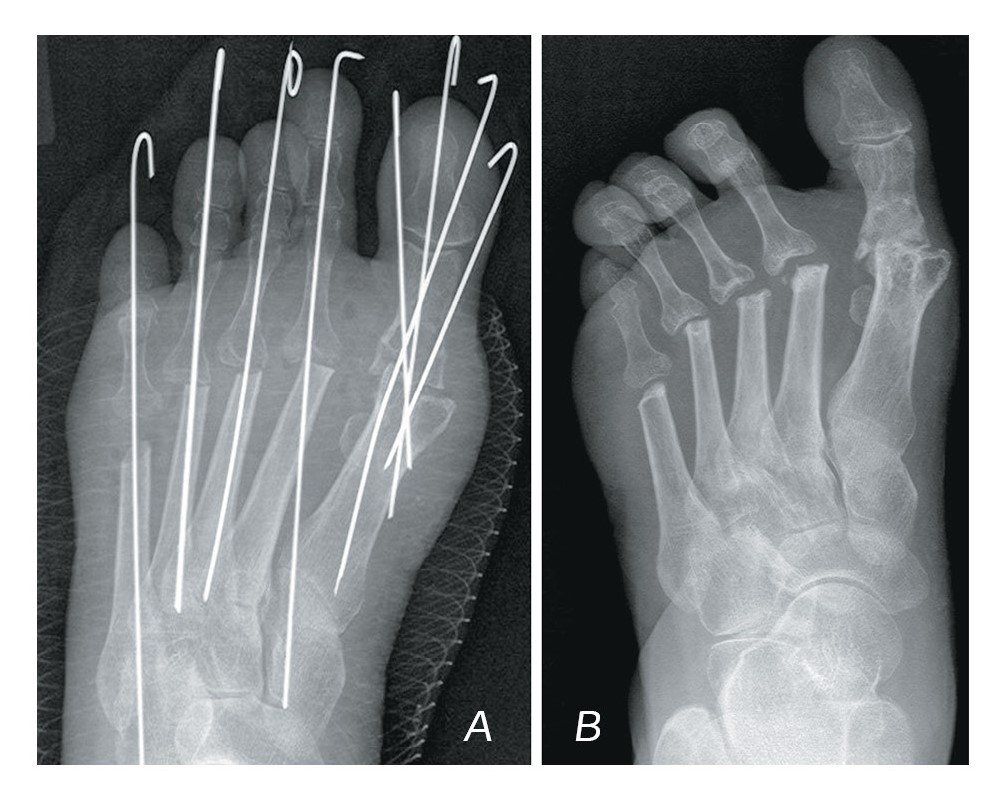

In four cases, instability of metal structures occurred. Two cases were noted in patients after arthrodesis of the first MTP joint with fixation with two Herbert’s cannulated screws. Two more cases were noted in patients after the Scarf and Akin osteotomies with the same type of fixation (Fig. 3). It is to be mentioned that the identified instability of metal structures did not affect the function of the foot, but in order to prevent more severe complications it was resolved to perform revision surgeries and remove the unstable metal structures. Following that, there were no complaints from the patients.

Figure 3. A – X-ray immediately after JPS (Scarf, Akin, Weil osteotomy); B – X-ray 6 months after JPS (aseptic necrosis of the head of the 2nd MB, instability of the Herbert screw, recurrence of the hallux valgus deformity of the 1st finger).

Рисунок 3. A – рентгенограмма сразу после ССО (остеотомии Scarf, Akin, Weil); B – рентгенограмма через 6 месяцев после ССО (асептический некроз головки второго ПК, нестабильность винта Герберта, рецидив вальгусной деформации первого пальца).